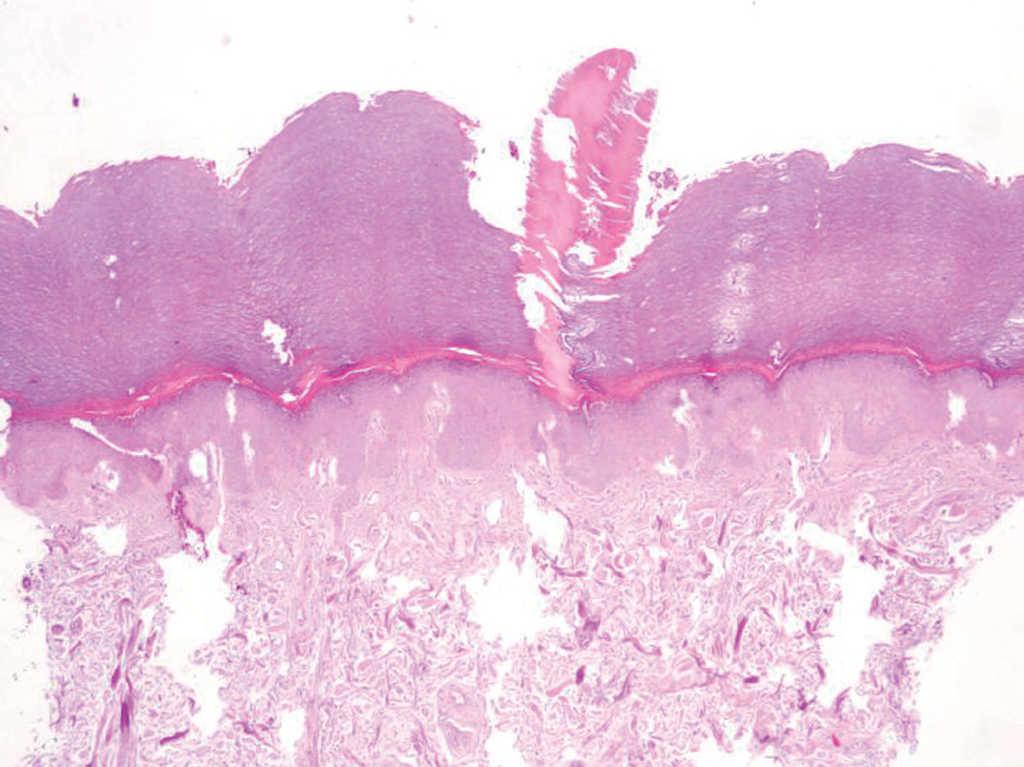

Se practicó una biopsia «en sacabocado» de 4 mm en la que se observaba una columna paraqueratósica en estrecha relación con el acrosiringo compatible histológicamente con nevo ductal y del ostium ecrino poroqueratósica (fig. 3). Un mes después y, a pesar de no estar recibiendo tratamiento, muchas de las lesiones habían desaparecido y otras persistían, aunque habían disminuido de tamaño. Se realizaron dos nuevas biopsias «en sacabocados». En diversos cortes de una de las piezas se observaba que existía relación entre la columna paraqueratósica y el ducto de las glándulas ecrinas. Sin embargo, en la mayoría de las preparaciones no se encontraba esta relación a pesar de haber seriado la muestra. Las pruebas analíticas, radiografía simple de tórax y tomografía computarizada (TC) toracoabdominal resultaron normales. Las lesiones permanecen estables desde su diagnóstico.

Fig. 3.--Columna de paraqueratosis bien delimitada sobre un estrato córneo adelgazado y que coincide parcialmente con un acrosiringio. (Hematoxilina-eosina, x10.)